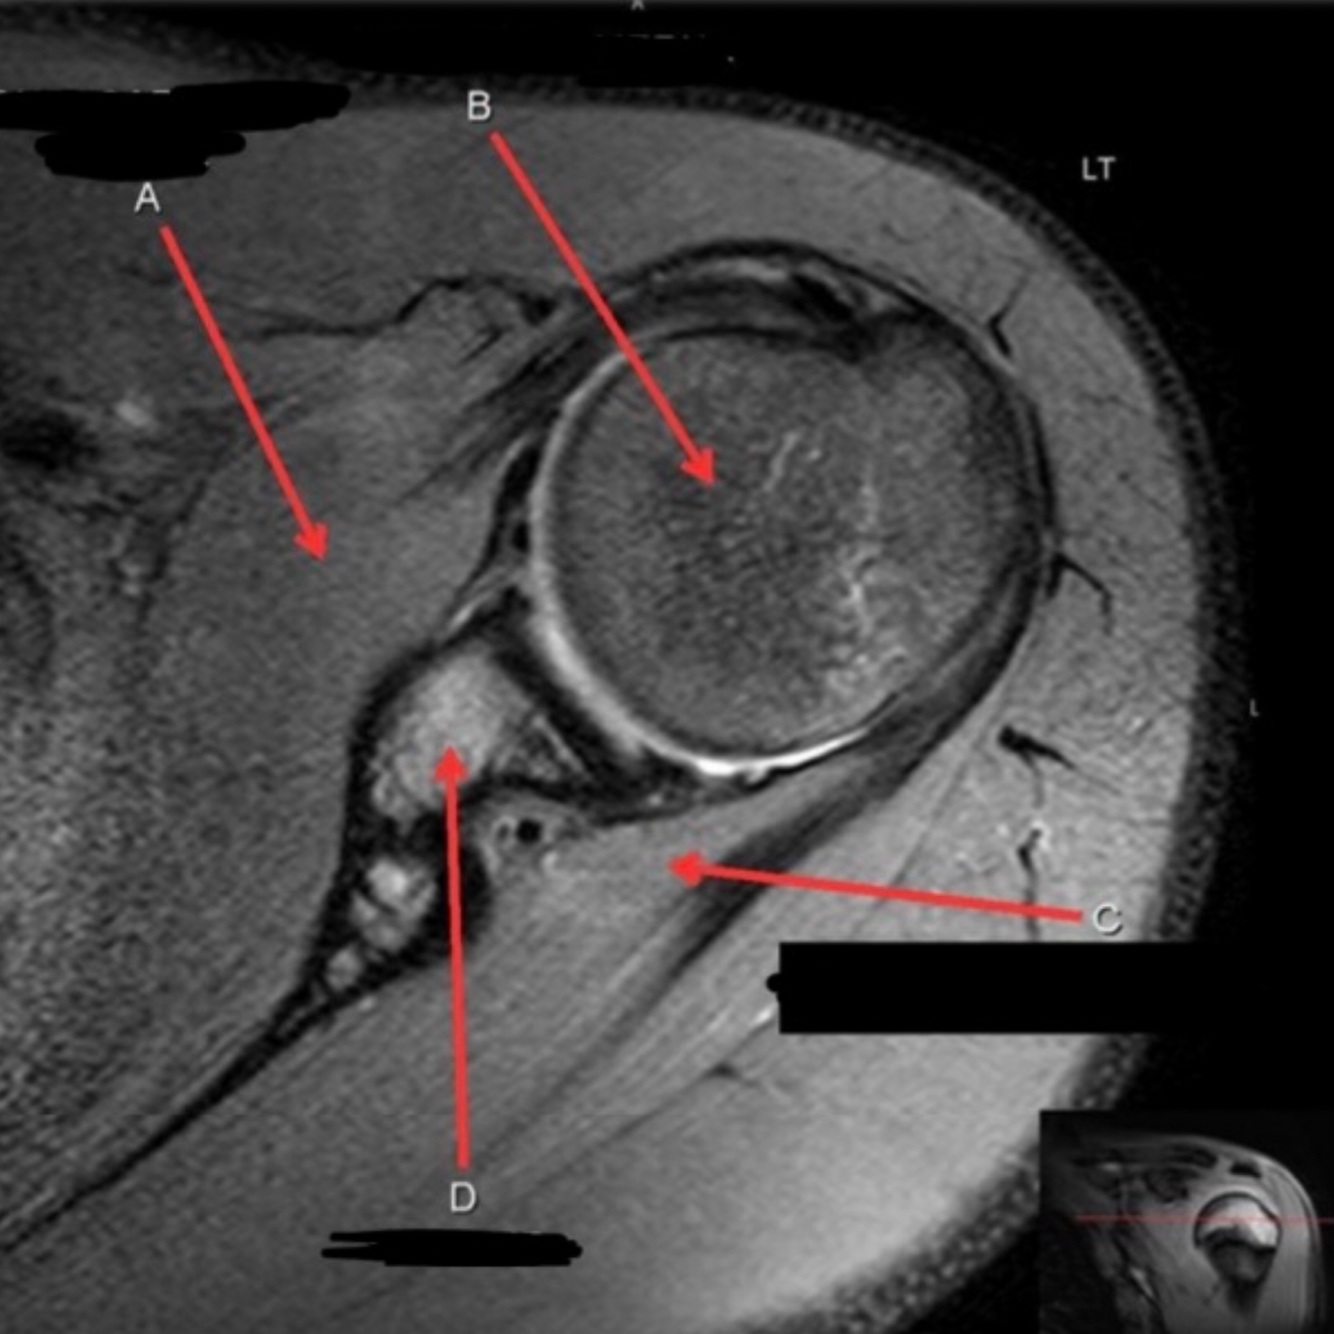

3

4

5

Perfectly

2

Q

What is letter B?

A

ACROMION

How well did you know this?

1